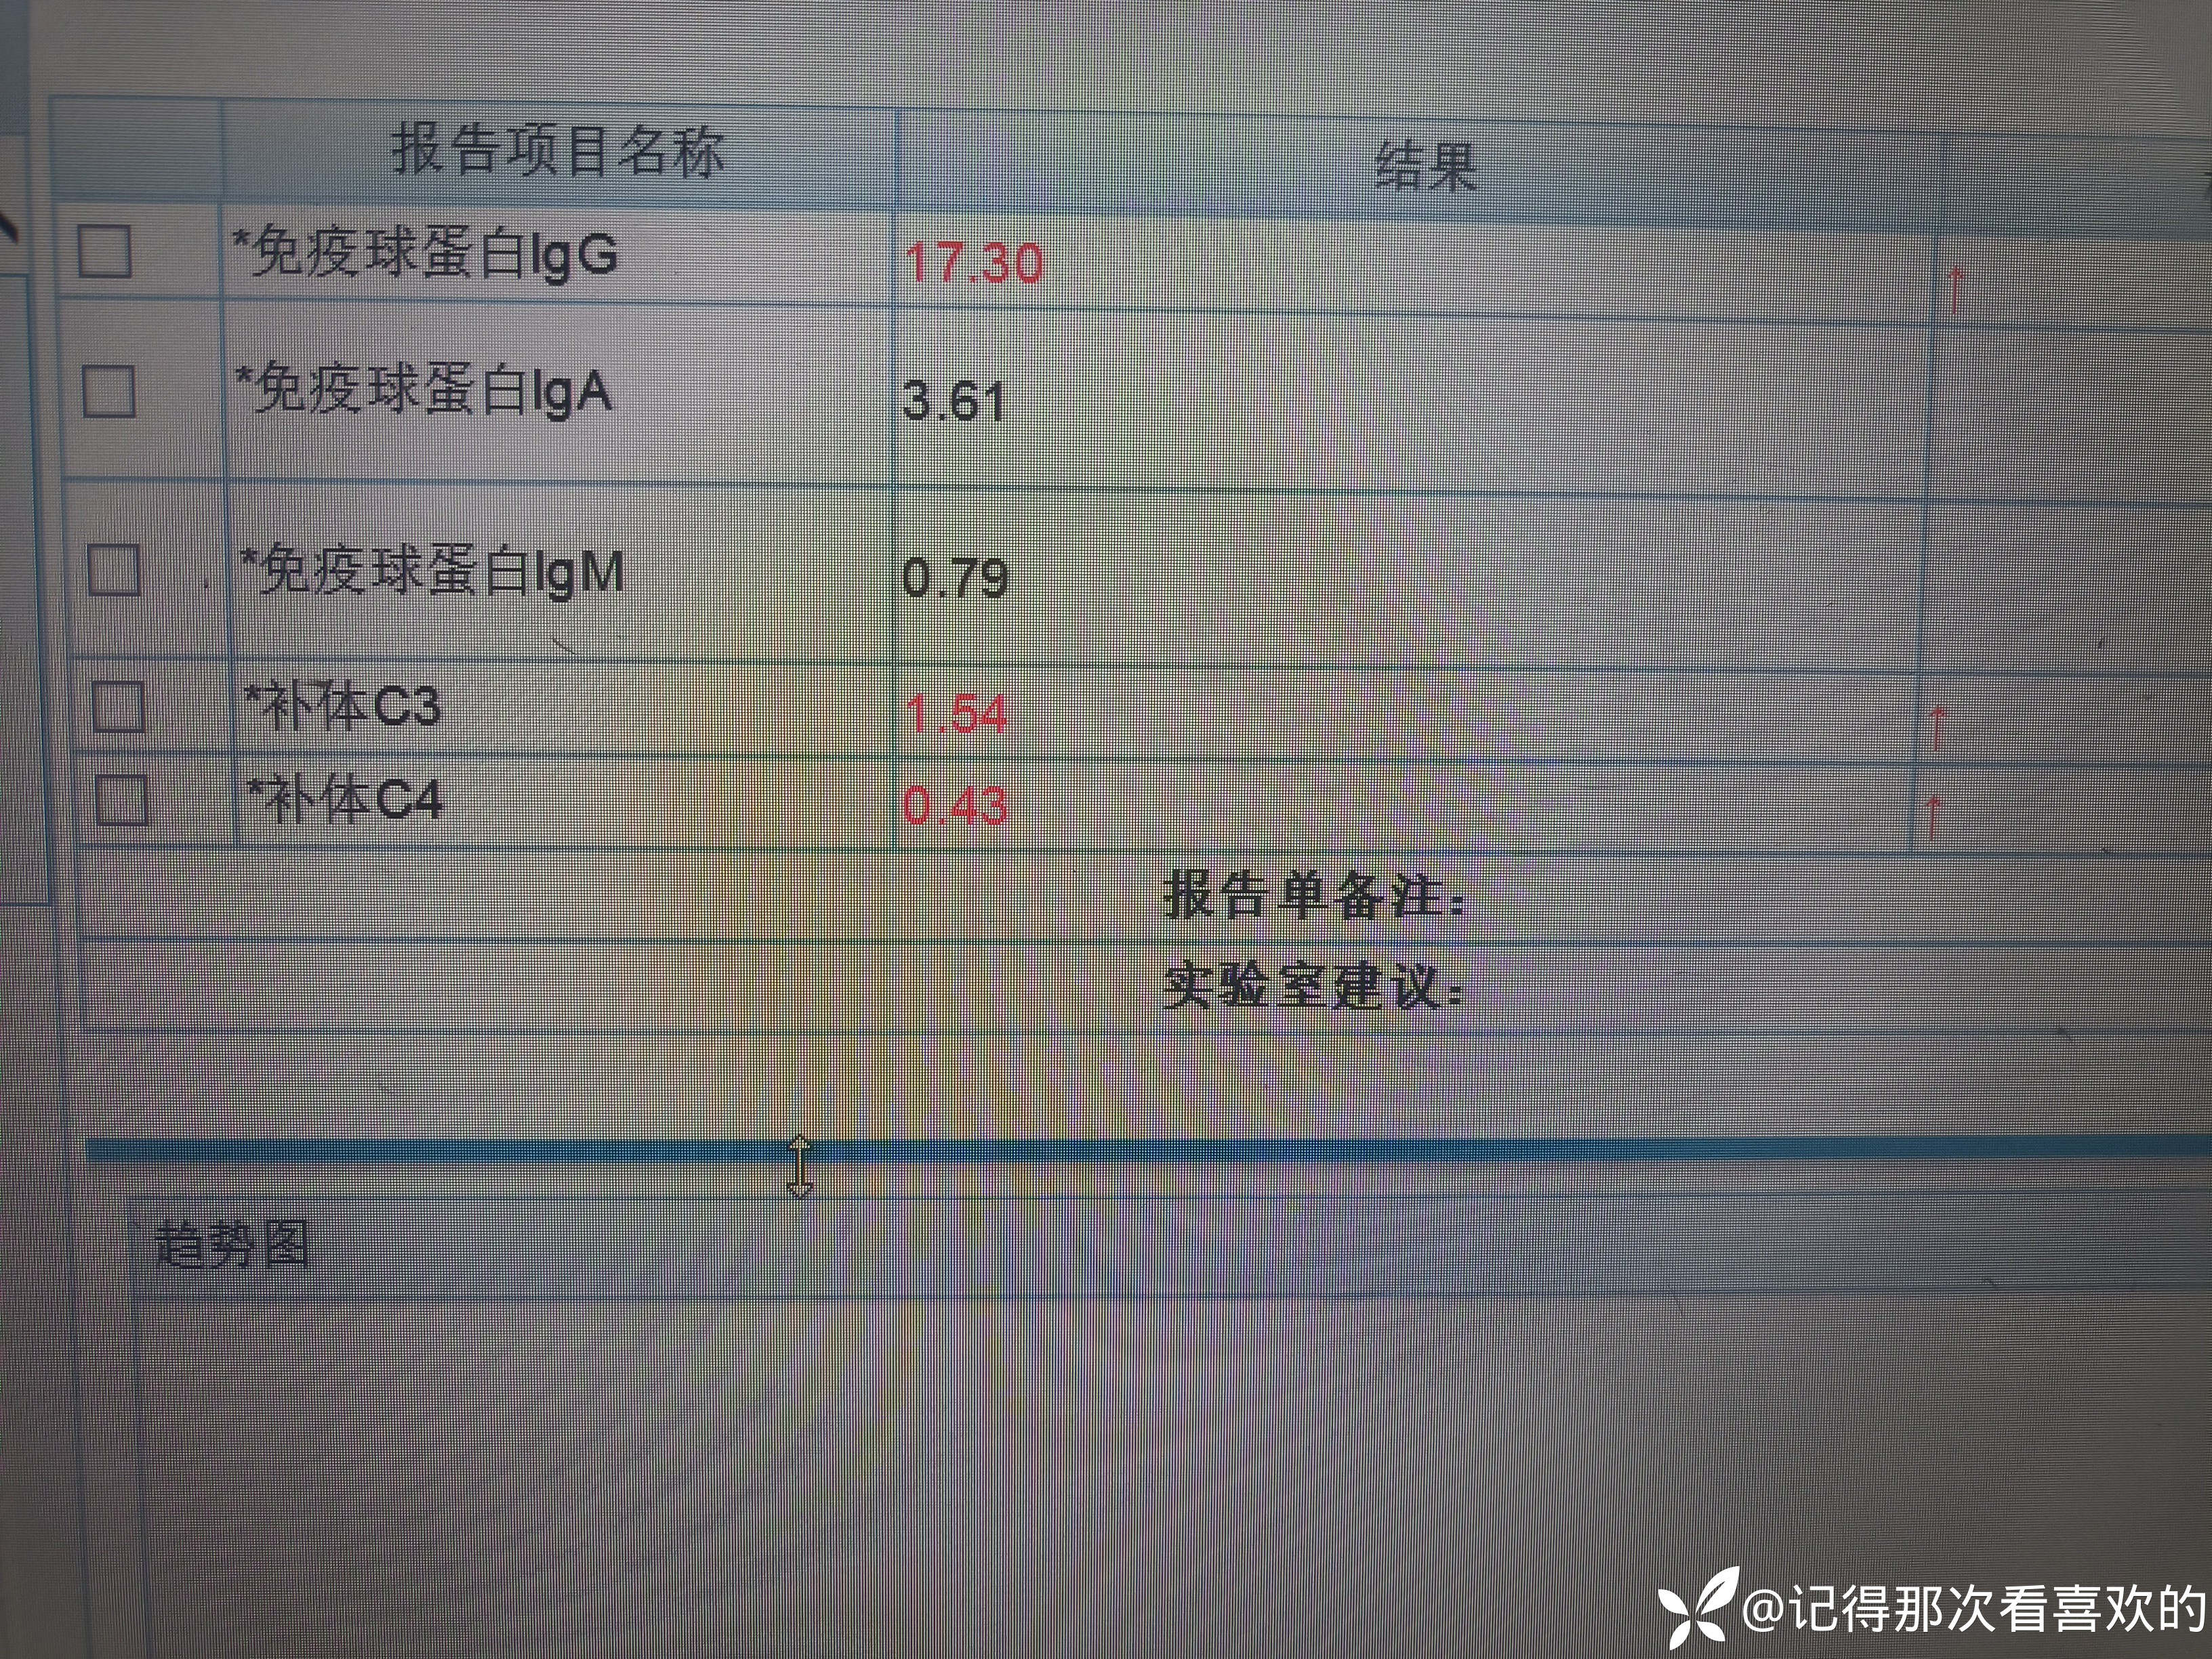

病例特点:患者钟某 男,14岁,以"髋、膝、足肿痛1年余,加重3日。"为主诉入院。现病史:缘于1年前无明显诱因出现左侧髋关节、双足跟、左踝关节、右足第一足趾关节肿胀、疼痛, 疼痛呈持续性,多于阴雨天、活动后症状加重,疼痛未向他处放射、转移,症状严重时行走困难。遂就诊于我科,查"HLA-B27(+)、CRP 70mg/L、骶髂MR:骶髂关节肿胀",诊断为"强直性脊柱炎",先后予皮下注射"司库其尤单抗150mg qw、阿达木单抗40mg q2w",上述症状较前好转,此后不规律用药,于半年前自行停用上述药物,未再规律随诊。3日前再发左膝、双肘关节肿痛,性质同前,程度较前加重,影响行走,伴有发热,体温最高达39℃,自行服用退烧药(具体不详)后体温较前下降,上述关节肿痛无明显改善。现为求进一步治疗,就诊我院,门诊拟"强直性脊柱炎"收住入院。体格检查:T36.6℃ P138次/分 R50次/分BP/120/68mmHg 专科情况:生命征平稳,神志清楚,双肺呼吸音清,未闻及干湿啰音,心律齐,各瓣膜听诊区未闻及杂音,全腹软,无压痛及反跳痛,未触及包块,双肘、左膝关节肿胀、压痛、触之皮温高。双下肢无浮肿,病理征未引出。

诊疗计划:1.入院予二级护理,监测血压、脉搏、呼吸。2.入院完善三大常规、凝血、生化、骶髂MR、彩超、CT、心电图等相关检查评估病情。3.治疗上暂予抗炎镇痛,辅以护胃治疗,待相关检查结果回报后进一步治疗,本次就诊拟行生物制剂治疗,予完善骨保护药物,传染病相关检查排除禁忌症,患者本次发病伴有发热达39℃,追问病史患者诉偶有干咳不适,目前已改善,予完善呼吸道病原学检查明确病情。4.患者Padua评分1分,属于发生VTE低危风险,实行VTE基本预防,动态评估Padua评分。5.已将目前病情及现有临床诊断以及存在疾病复杂性、个体的差异性、对治疗的反应不同、鉴于目前医学技术水平有限,和下一步相关诊疗详细充分告知患者家属,取得家属的理解并同意配合下一步诊疗及检查。6.NRS-2002评分3分,目前患者营养状态尚可,进食情况尚可,根据病情变化动态评估。